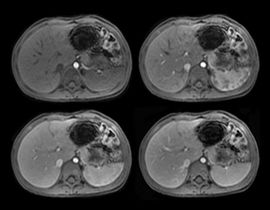

BodyWorks für einen der am schnellsten wachsenden Bereiche der MRT. Diese umfassende Bibliothek ermöglicht die Bildgebung von Abdomen und Becken und gestattet dem Benutzer die flexible Anpassung an unterschiedliche Patiententypen.

Auto Navigator ist die Lösung von GE zur Bekämpfung von Atembewegungen bei abdominellen Aufnahmen. Dieser Ansatz für freie Atmung ist mit mehreren Pulssequenzen kompatibel, darunter Diffusion, PROPELLER MB, MRCP und dynamische T1-Bildgebung.

Die vier Bilder zeigen dynamische T1-Aufnahmen mit PB-Navigator, die dem Patienten das freie Atmen ermöglichen und gleichzeitig den Kontrast in schnellen Zeitphasen erfassen. Einschätzungen der gesamten Wirbelsäule lassen sich mit T2 frFSE-Routineaufnahmen problemlos vornehmen.